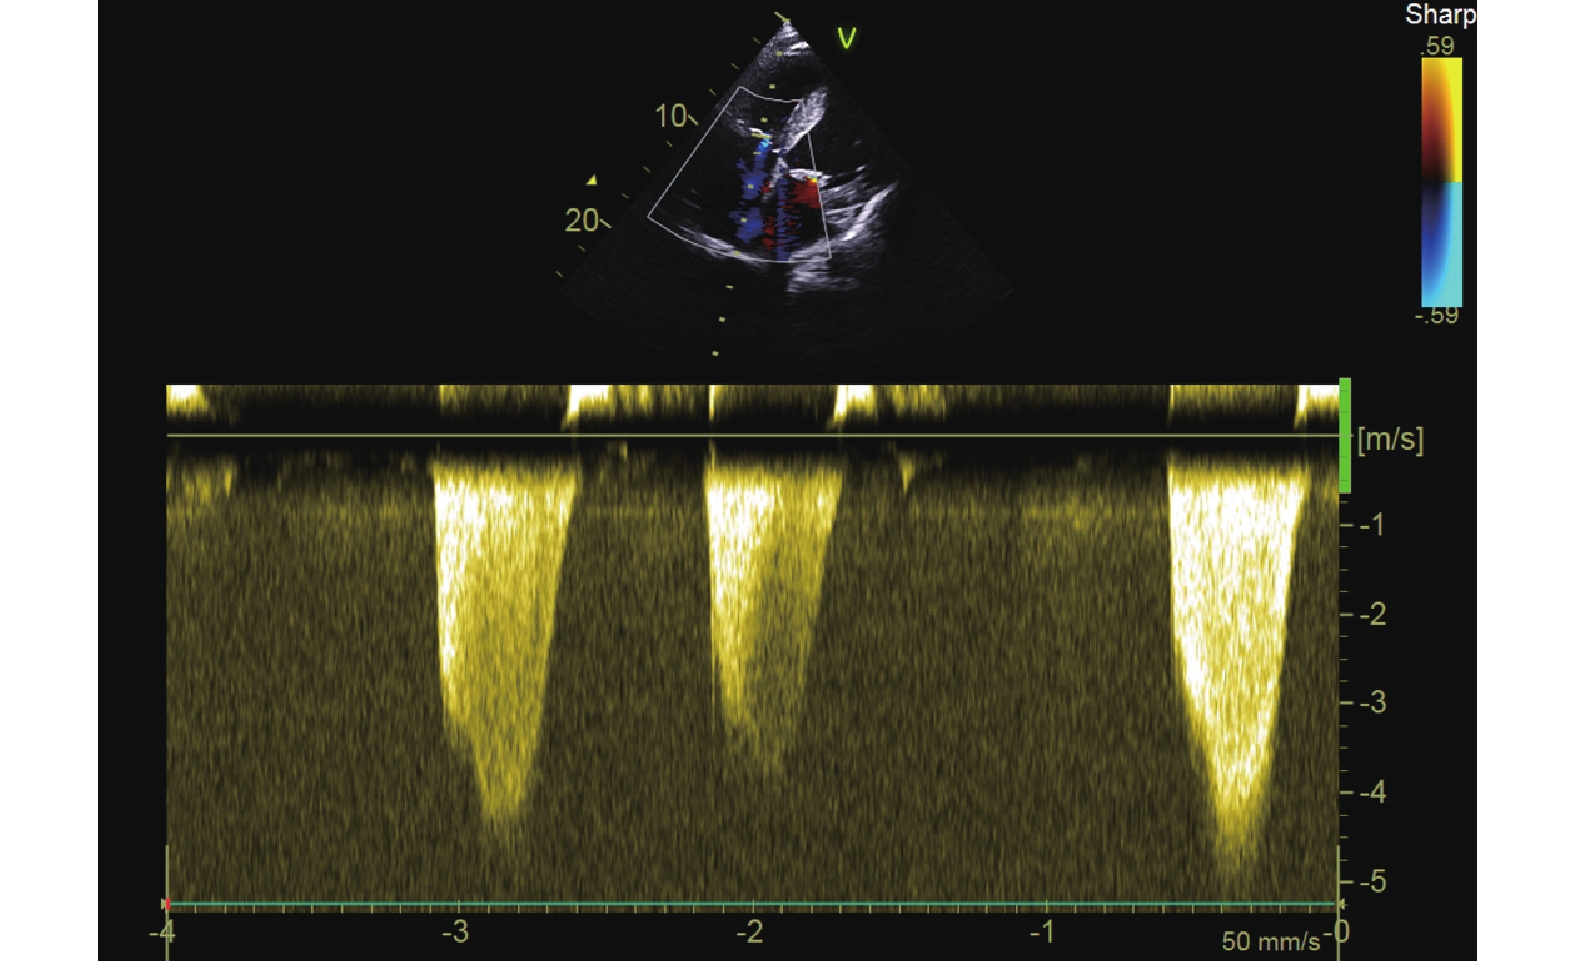

病例介紹 患者,男,63 歲,因“反復呼吸困難 11+ 年,加重伴雙下肢水腫 2 周”于 2018 年 1 月 31 日急診入四川大學華西醫院。入院時體格檢查:體溫 36.5℃,脈搏 56 次/min,呼吸頻率 28 次/min,血壓 80/45 mm Hg(1 mm Hg=0.133 kPa)。患者神志清楚,急性病容,皮膚呈青紫花斑狀改變,心率 56 次/min,端坐呼吸,雙側呼吸運動增強,呼吸急促,雙下肺聞及干濕啰音。入院后急查腦鈉尿肽前體 11 215 pg/mL;心肌標志物:肌紅蛋白 53.08 ng/mL,肌酸激酶同工酶質量 5.02 ng/mL,肌鈣蛋白 T 101.9 ng/L,排除急性心肌梗死;血紅蛋白 158 g/L,排除急性失血性休克。急診心臟彩色多普勒超聲示主動脈瓣平均跨瓣壓差為 47 mm Hg,主動脈瓣前向血流峰值流速為 4.2 m/s,估測肺動脈壓力 86 mm Hg,左心室射血分數 45%(圖 1)。美國胸外科醫師協會評分 9.985%。考慮主動脈瓣重度狹窄合并急性失代償性心力衰竭、心源性休克。予以無創呼吸機輔助通氣后,患者仍有明顯呼吸困難,血管活性藥物難以改善休克血壓。心臟團隊討論后認為患者為外科手術風險極高危,擬于 2018 年 1 月 31 日行急診經導管主動脈瓣置換術(transcatheter aortic valve replacement,TAVR)。因考慮患者為極高危患者,術前通知體外膜肺氧合團隊備臺。因患者無法完成 CT 檢查,采用經食管超聲心動圖(transesophageal echocardiography,TEE)做術前評估(圖 2),結果顯示:主動脈瓣環周長為 94.6 mm,平均內徑為 30.13 mm,竇部周長為 116.6 mm,竇管結合部周長為 96.8 mm,左冠狀動脈高度為 17.0 mm,右冠狀動脈高度為 18.76 mm。麻醉評估后采取插管全身麻醉方式,術中以 TEE 監測。使用 TAV8-21/26 mm 球囊進行預擴,同時行主動脈根部造影,未見明顯反流,球囊擴張后患者血壓 112/60 mm Hg。根據 TEE 測量結果及預擴球囊大小,選擇 29 mm Venus A 瓣膜(杭州啟明醫療器械有限公司)。瓣膜釋放后造影示無明顯瓣周漏,有創峰值壓差 7 mm Hg(圖 3)。患者術后恢復良好,院內未發生不良事件,出院時臨床癥狀完全緩解。2018 年 3 月復查心臟彩超示主動脈瓣平均跨瓣壓差為 9 mm Hg,主動脈瓣前向血流速度峰值 2.0 m/s,左心室射血分數提升至 49%,估測肺動脈壓力 54 mm Hg。

提示重度主動脈瓣狹窄